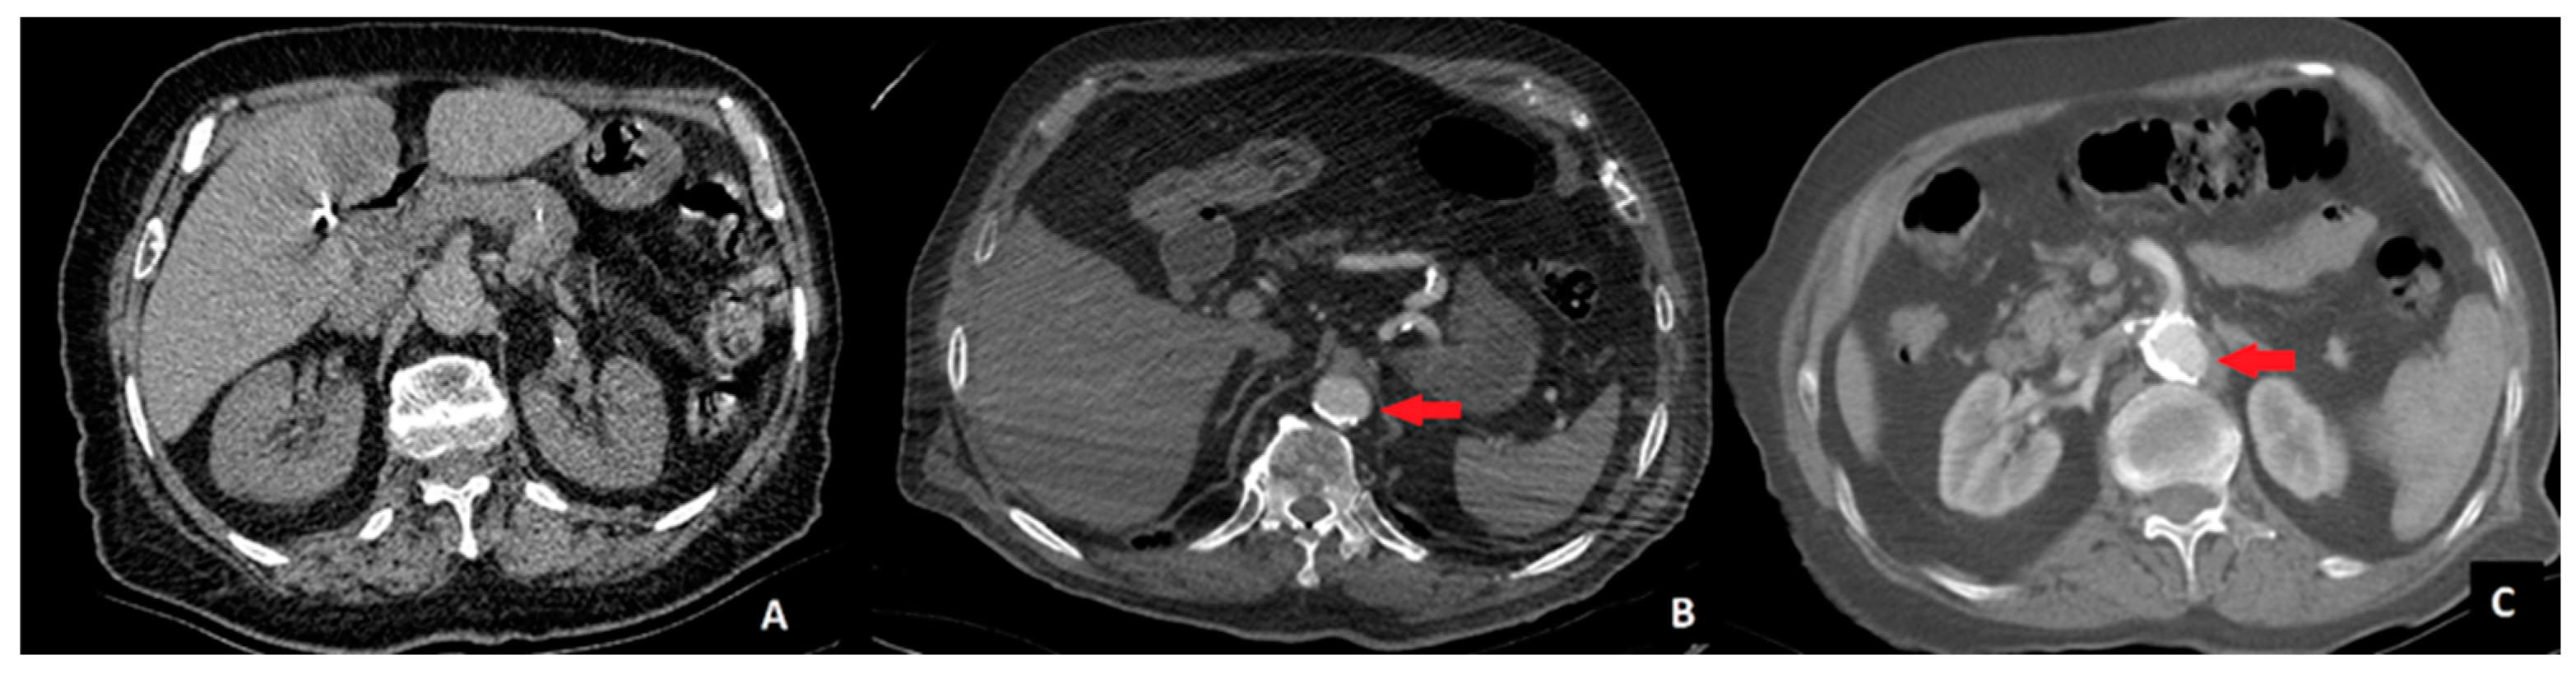

To ensure consistency, radiologists independently assessed all scans, and interobserver agreement was measured using Cohen’s kappa coefficient (κ). In cases of disagreement, a consensus meeting was conducted to finalize classification. This approach minimized variability and improved reliability in AC grading. Aortic calcification was assessed in the segment between the celiac trunk and the aortic bifurcation using axial and coronal CT images. Aortic calcification was classified into three stages based on the extent of calcified plaques encircling the aortic lumen. Stage 0 was defined as the absence of any detectable calcification. Stage 1 was assigned when calcification occupied less than 50% of the aortic circumference. Stage 2 was defined as calcification occupying more than 50% of the aortic circumference. A visual example of each calcification stage is provided in Figure 1.

Figure 1. Computed tomography images of patients. A—no calcification (Stage 0), B—calcified area less than 50% of the aortic circumference (Stage 1), and C—calcified area more than 50% of the aortic circumference (Stage 2). The area of calcification is indicated by a red arrow.